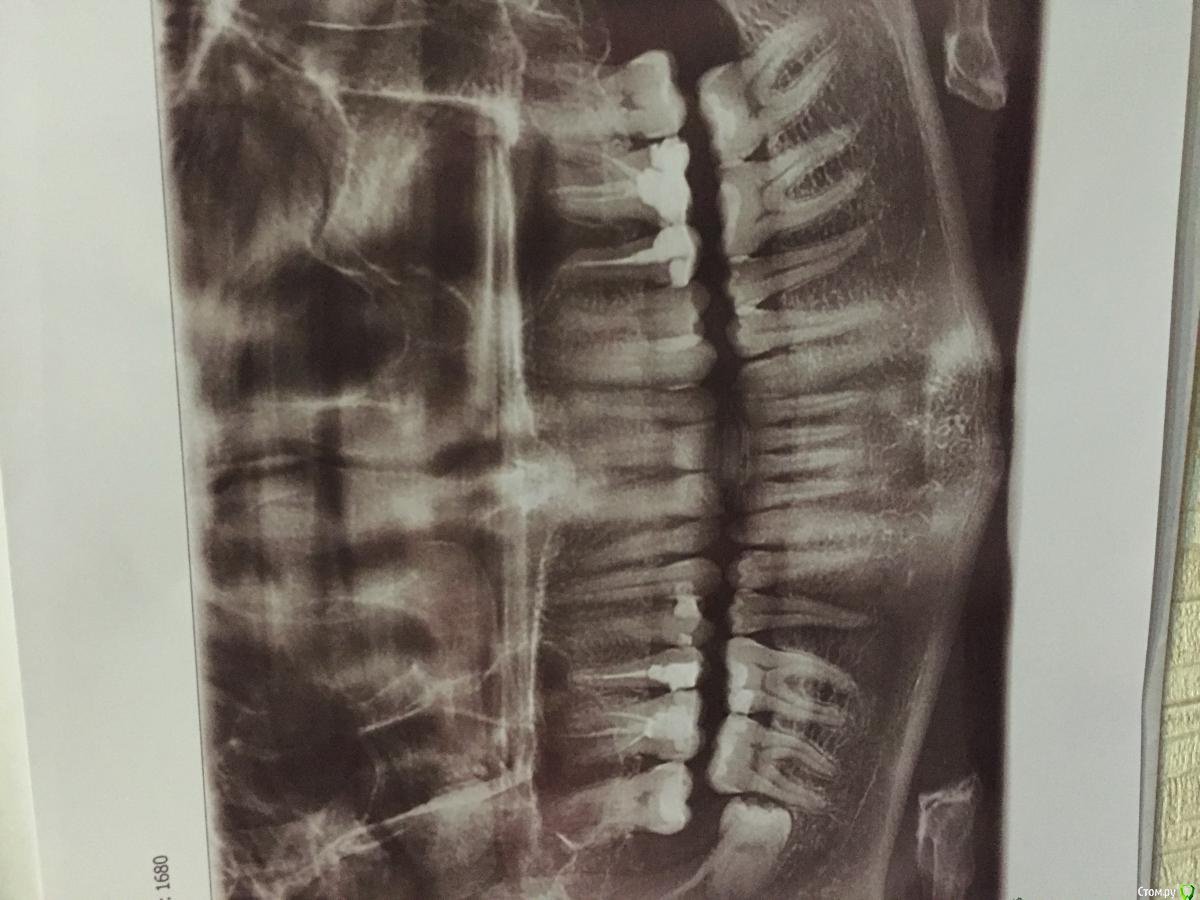

Andrey1307 Опубликовано 16 марта, 2016 Поделиться Опубликовано 16 марта, 2016 Доброго времени суток, уважаемые стоматологи. Что можете сказать по снимку? Какие Зубы требуют лечения? Беспокоит боль и реакция на холодное и горячее в 16 зубе. Ссылка на комментарий

red_butler Опубликовано 16 марта, 2016 Поделиться Опубликовано 16 марта, 2016 Что можете сказать по снимку?Он перевернут 2 Ссылка на комментарий

Andrey1307 Опубликовано 17 марта, 2016 Автор Поделиться Опубликовано 17 марта, 2016 исправил Ссылка на комментарий